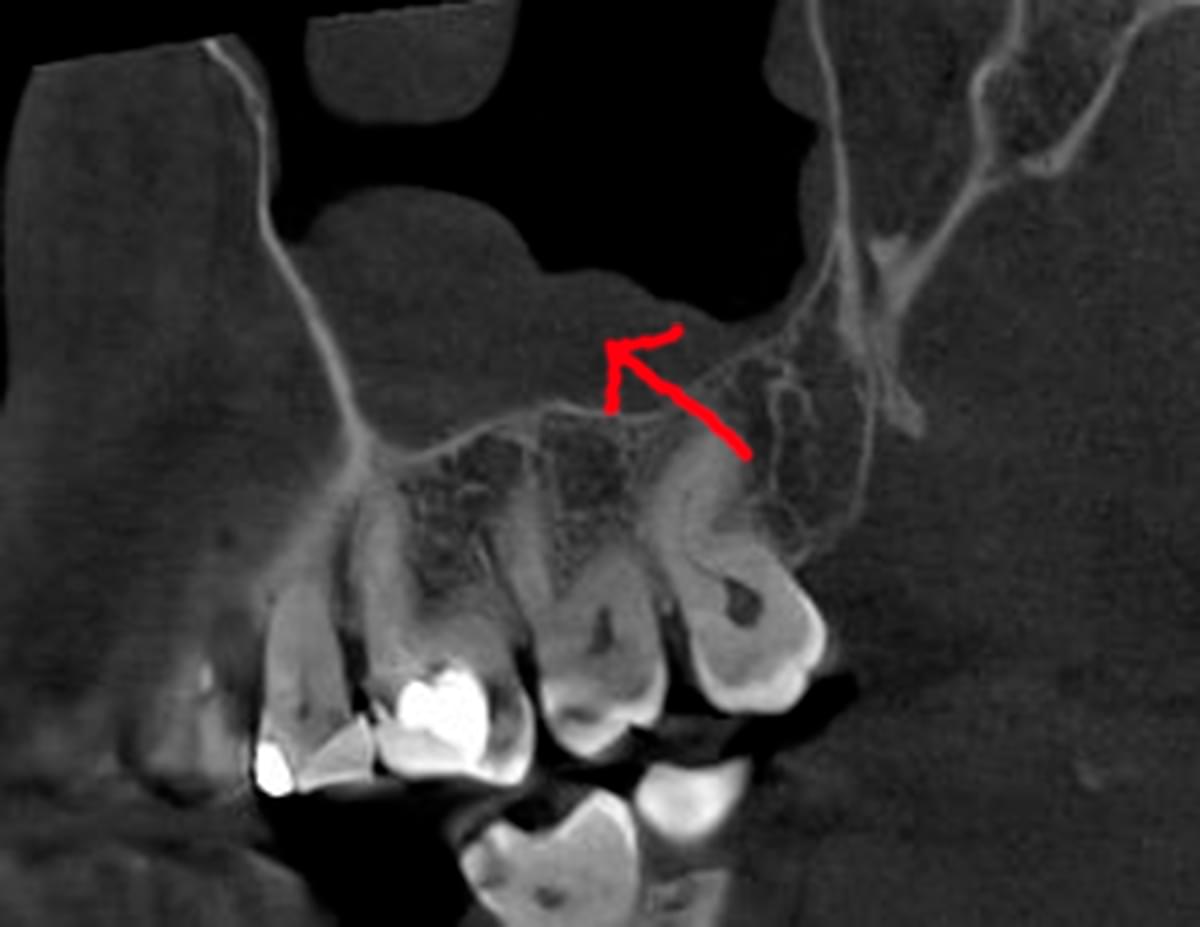

Коли коріння «ховає сюрпризи» - Корені зубів часто мають складну кривизну, гачкоподібні закручення або розгалуження, які на звичайному 2D-знімку накладаються один на одного, створюючи ілюзію прямого каналу. На плоскій картинці неможливо побачити реальний об'єм та напрямок вигину, що критично важливо при видаленні «зубів мудрості» або ендодонтичному лікуванні. КТ MyRay дає змогу лікарю заздалегідь побачити 3D-геометрію кожного кореня, оцінити його близькість до нижньощелепного нерва чи гайморової пазухи та підібрати правильну тактику роботи. Це мінімізує ризики поломки інструменту в каналі або травмування сусідніх структур, перетворюючи складну хірургію на прогнозовану процедуру.

Часто причиною зубного болю є гайморит, і навпаки — причиною запалення пазух є хворий зуб. На звичайному знімку пазуха виглядає як темна пляма. На КТ ми бачимо стан слизової, наявність кіст або сторонніх тіл (наприклад, залишків пломбувального матеріалу), що критично важливо для правильного діагнозу.